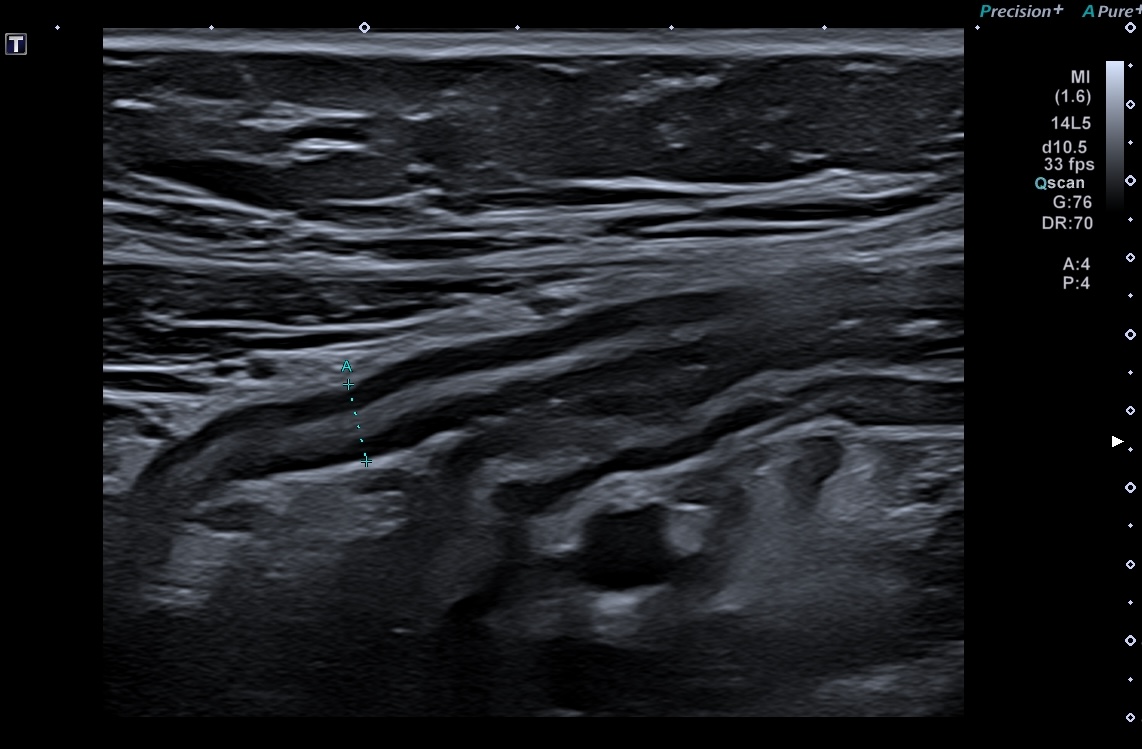

les modifications vont faciliter le repérage de l'anse inflammée et rendre la paroi visible

----> Plus l'inflammation est intense plus les lésions sont faciles à voir.!

Epaisseur > 3 mm